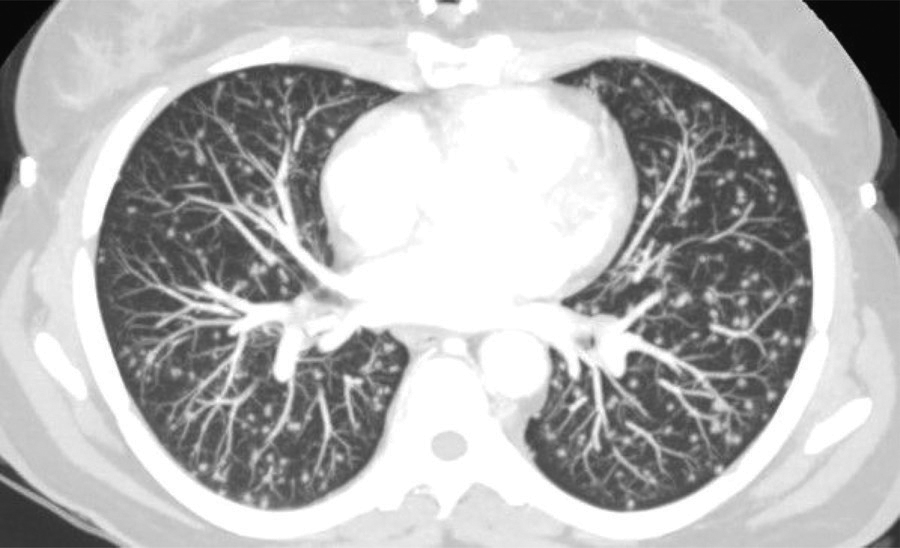

Figure 3

Computed tomography parenchymal window of the lung